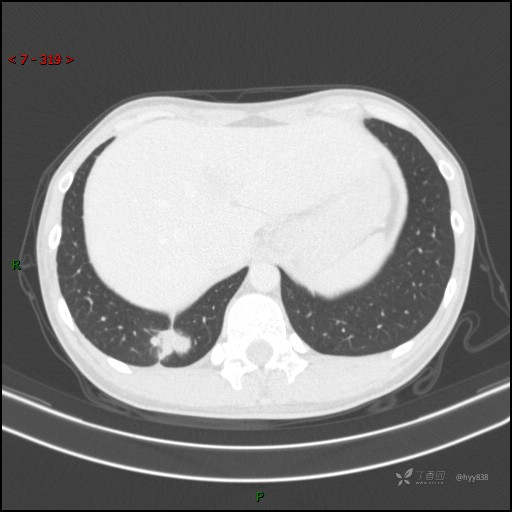

胸部CT平扫